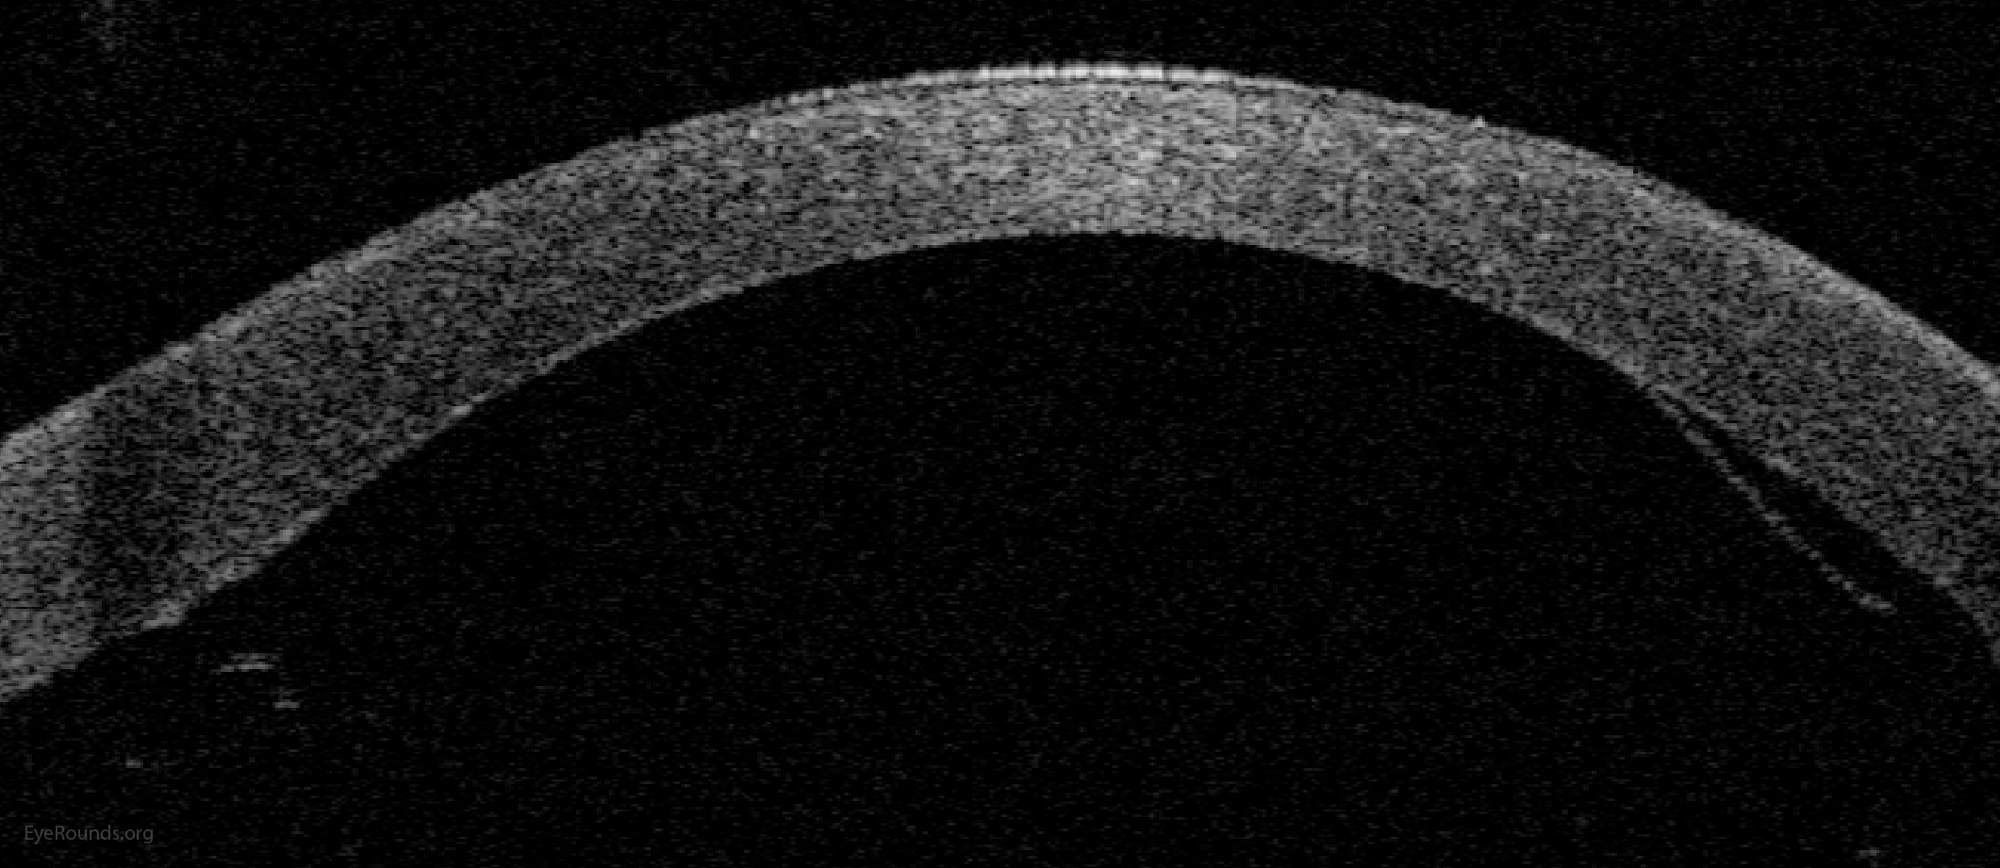

OCT showing graft lifting is limited

Figure 2: Anterior segment optical coherence tomography demonstrating a limited, peripheral graft edge lift one week after DMEK surgery (right side of image). The attached portion of the graft mimics normal anatomy due to the precise 1-to-1 replacement of tissue with DMEK.